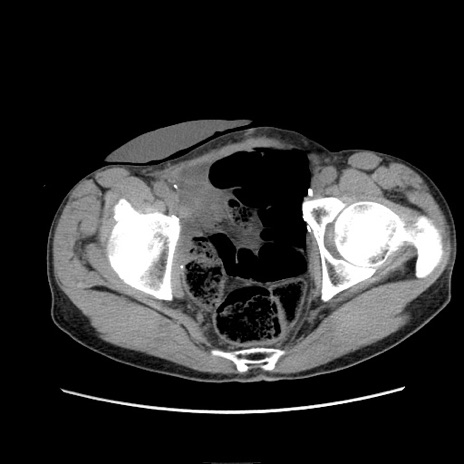

冠状断像

症例11(横断像)

【症例】 60歳代男性

【主訴】 下腹部痛

【現病歴】 本日夜中より下腹部痛の症状認め、受診。

【既往歴】 膀胱癌(膀胱全摘+尿管皮膚瘻術) 、胃癌術後

【身体所見】 BT 35.3℃、PR 58/min、BP 136/98mHg、腹部平坦、軟、腸蠕動音±、ストマ留置あり、左上腹部~正中部に圧痛あり、反跳痛なし。

【データ】WBC 5100、CRP0.01